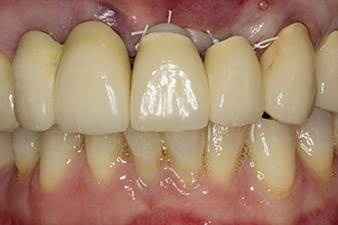

При първоначалното лечение на пациентката, зъби 21, 22 и 23 са шинирани в корона, вече на 19 години, които са закрепени към имплантите на позиции 12/11 чрез надстройка (Фиг. 2).

Рентгеновата снимка показа хоризонтална загуба на кост около зъби 21 и 22 (Фиг. 1). Когато короната е отстранена, тези зъби са били неумишлено екстрахирани с нея.

Зъб 23 разкрива хоризонтално-коронарна фрактура и е възстановен с коронарно изграждане за временно възстановяване. Планът за лечение е да се постави циркониево-оксиден мост върху съществуващите импланти в позиции 12 и 11 и да се поставят два нови импланти в позиции 22 и 23.